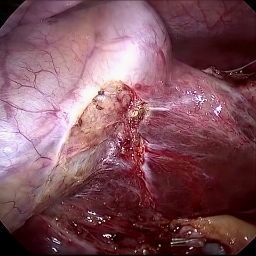

Refer to caption (a) Input Refer to caption (b) DIACMPN Refer to caption (c) Desmoke-LAP Refer to caption (d) PFAN Refer to caption (e) MITNET Refer to caption (f) Salazar Refer to caption (g) Dehamer Refer to caption (h) Ours Refer to caption (i) Target

Figure 3: Comparison of different methods on the LSD3K dataset.

IV-C2 Qualitative Analysis

Figures 3 and 2 provide a visual comparison of the desmoking results on challenging images from the test sets. The visual results corroborate our quantitative findings. DCP not only fails to remove the dense smoke but also introduces severe color distortion. CNN-based methods like FFA-Net and MSBDN successfully remove a large portion of the smoke but tend to either leave behind a thin layer of residual haze or over-smooth the image, losing critical textural details of the tissue and surgical instruments. The Transformer-based methods, DehazeFormer and PFAN, produce significantly better results by restoring more details. However, they can sometimes struggle with non-uniform smoke distribution, resulting in regions with unnatural brightness or minor artifacts.

In stark contrast, our RGA-Net generates visually superior results that are remarkably close to the ground-truth images. It effectively removes even the densest plumes of smoke while simultaneously preserving fine-grained details, such as blood vessels, tissue textures, and reflections on surgical tools. Furthermore, the color and illumination of the restored scene appear more natural and consistent, which is a direct benefit of our model’s ability to handle both local and global features through its hybrid attention and cross-gating mechanisms. This enhanced visual clarity is crucial for improving the surgeon-robot interface in real-world clinical applications.